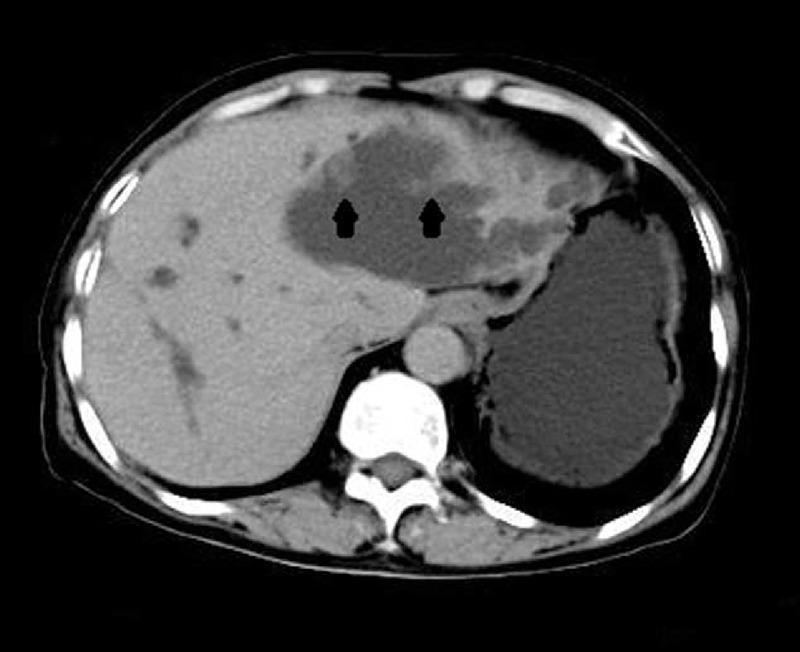

Hepatobiliary cystadenoma complication with congenital choledochal cyst is extremely rare and has never been reported in literatures so far.The aim of the study was to investigate the disease arrangements by analyzing the case and performing a systematic review of the literature.This case report documents the details and clear patterns of the patient. A 65-year-old woman with fever (39.2°C), nausea, vomiting, and chronic hepatitis B imaging demonstrated a left hepatic multilocular cystic mass and cystic dilated common bile duct.A regular left hemihepatectomy was performed with resection of the entire tumor and choledochal cyst.The surgical margins were negative and a final diagnosis of hepatobiliary cystadenoma complicated with congenital choledochal cyst was established. The patient had an uneventful postoperative recovery and liver function returned to normal levels.Main lessons learned from this case are: the awareness should be raised about the disease to avoid misdiagnosis; preoperative ultrasonography, computed tomography, magnetic resonance imaging, and magnetic resonance cholangiopancreatography play an important role in detecting the lesion; the scope and timing of the surgery should be determined, which provide the chance of cure to complete resection of the tumor.

肝内胆管囊腺瘤合并先天性胆管囊肿极为罕见,迄今为止文献中尚未见报道。本研究旨在通过分析该病例并对文献进行系统回顾来探讨疾病的情况。本病例报告记录了患者的详细情况及明确特征。一名65岁女性,伴有发热(39.2℃)、恶心、呕吐,慢性乙型肝炎影像学检查显示左肝多房囊性肿块及胆总管囊性扩张。行规则性左半肝切除术,完整切除肿瘤及胆管囊肿。手术切缘阴性,最终诊断为肝内胆管囊腺瘤合并先天性胆管囊肿。患者术后恢复顺利,肝功能恢复至正常水平。从此病例中得到的主要经验教训是:应提高对该疾病的认识以避免误诊;术前超声、计算机断层扫描、磁共振成像及磁共振胰胆管造影在检测病变方面发挥重要作用;应确定手术范围和时机,这为肿瘤的完整切除提供治愈机会。